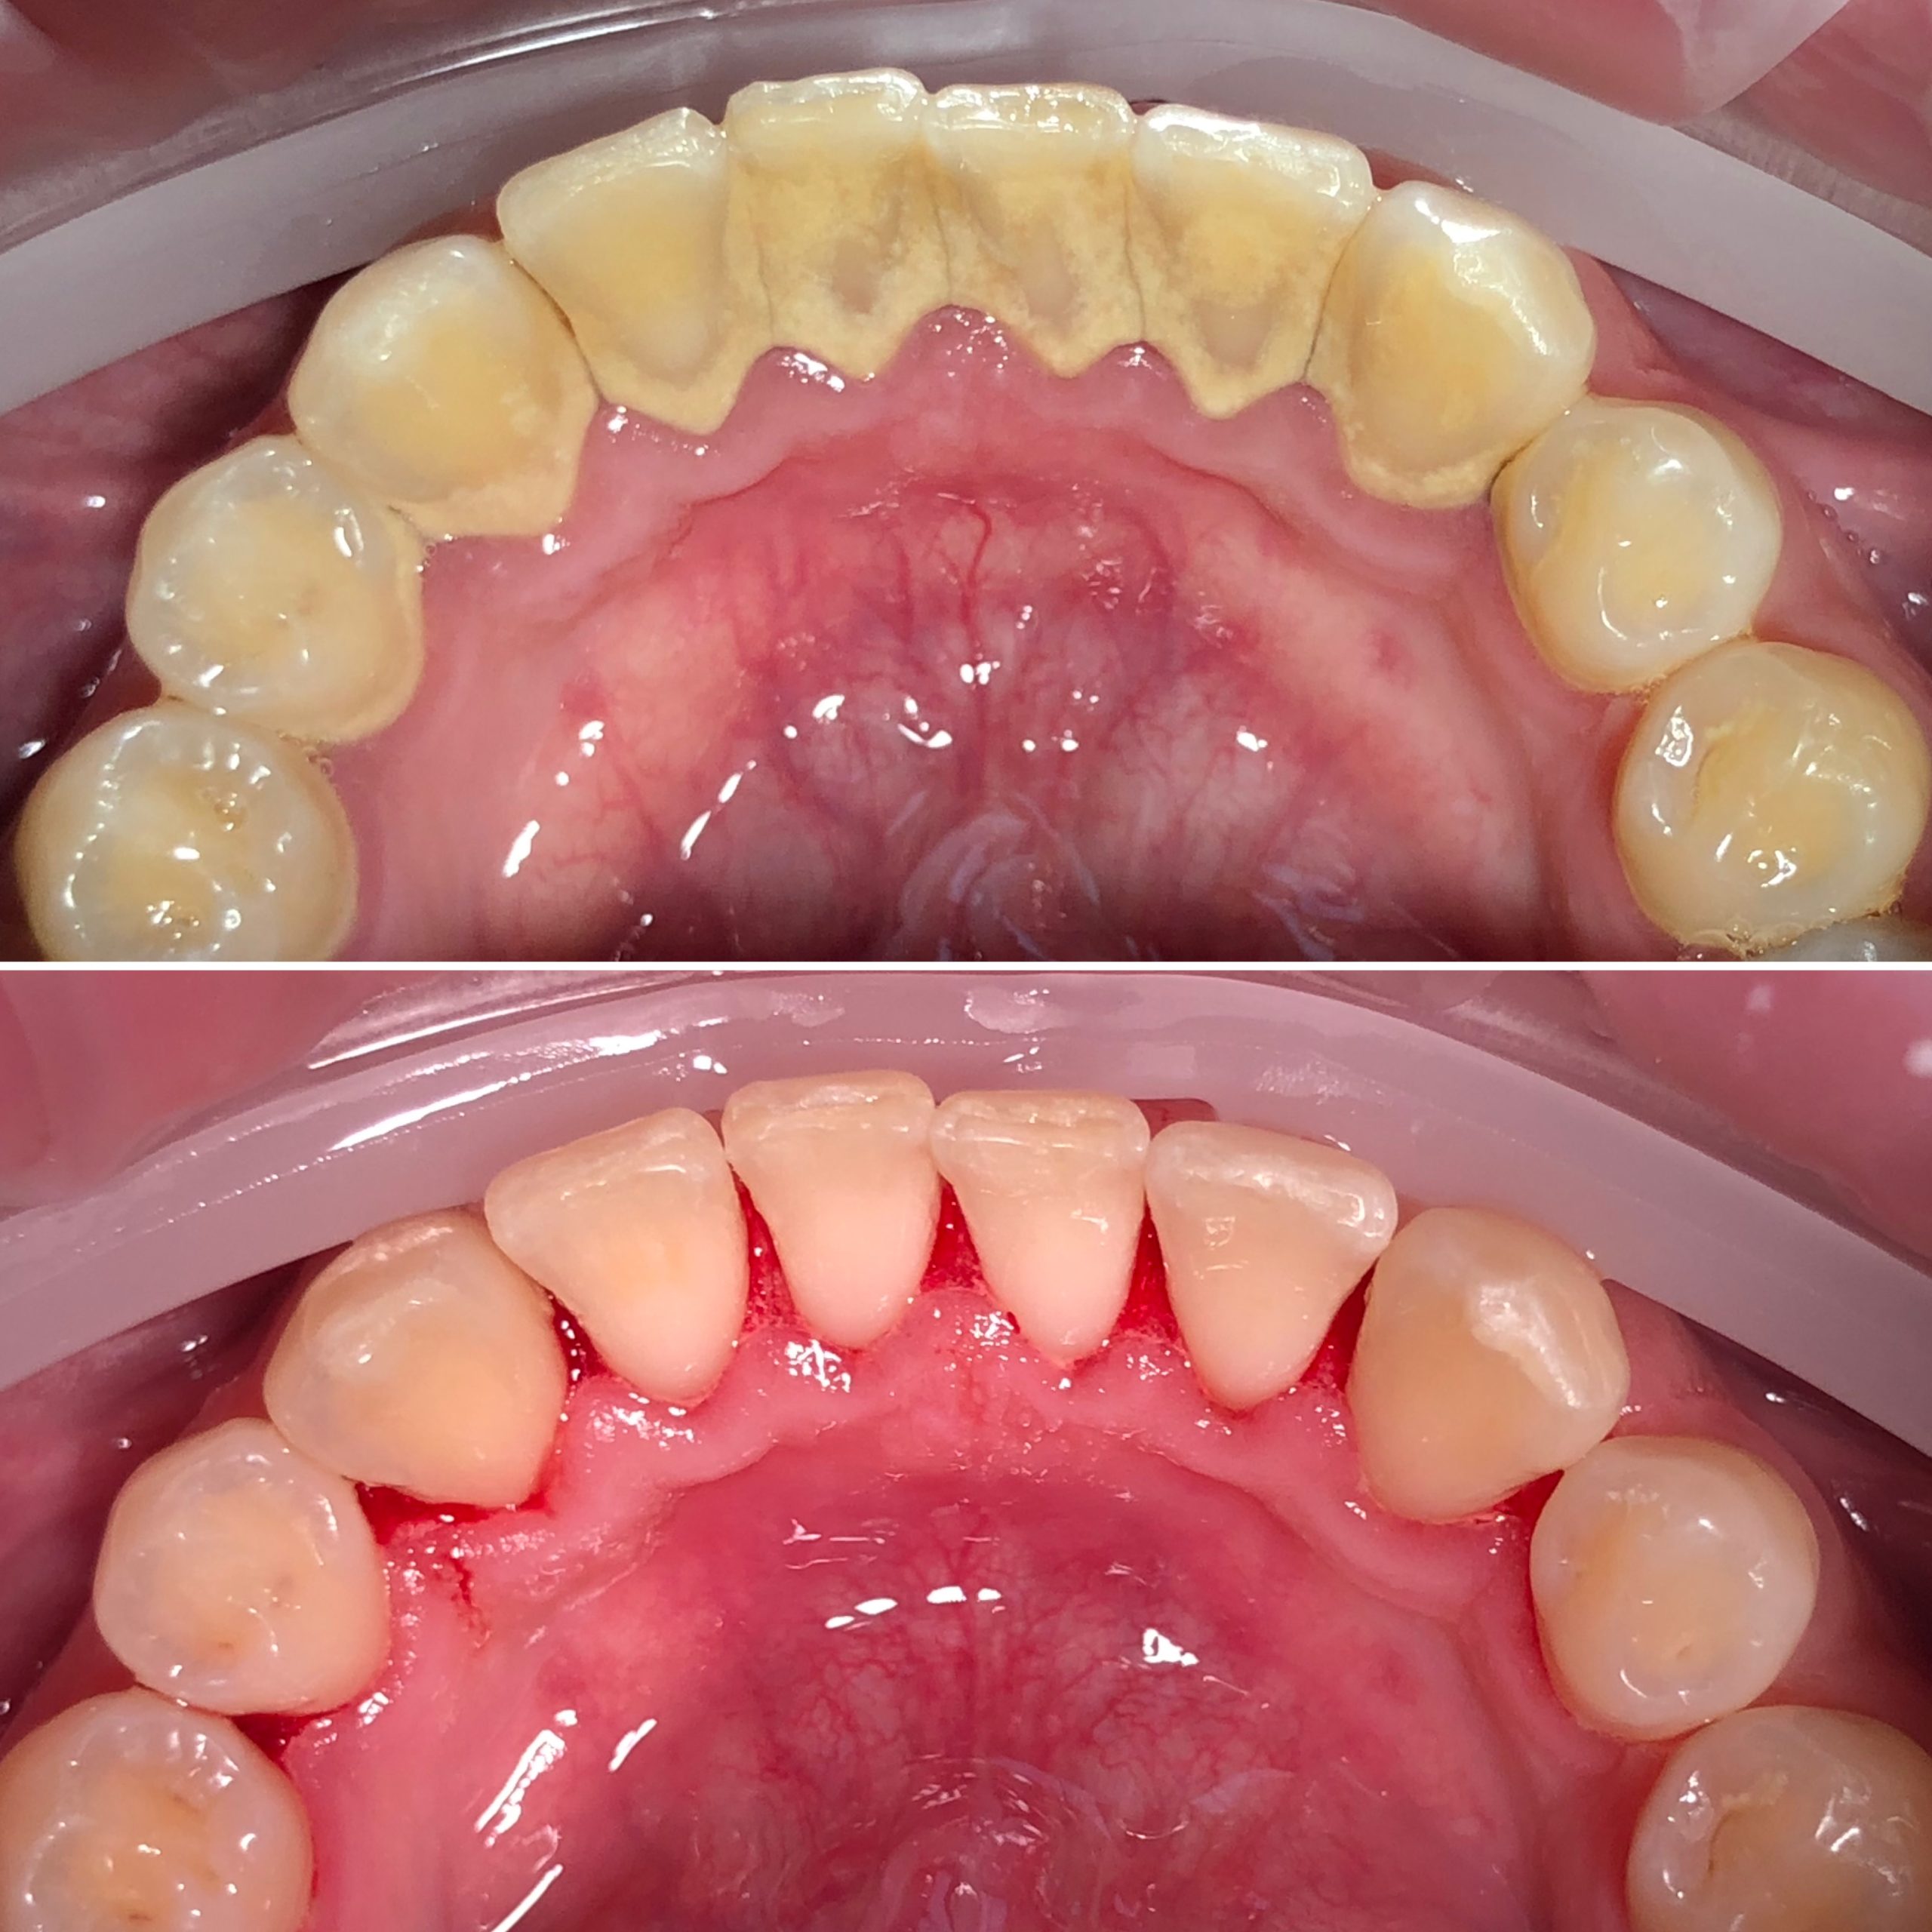

• Фотопротокол

• Профессиональная гигиена полости рта и подбор индивидуальных средств гигиены, профилактика стоматологических заболеваний